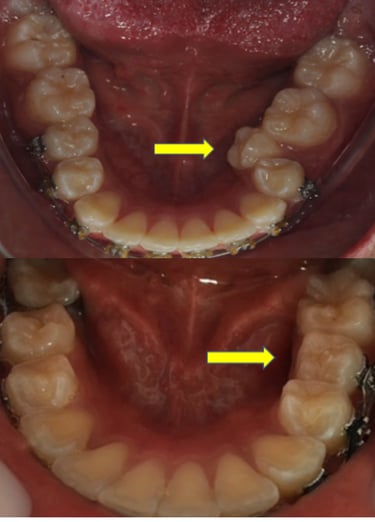

EVOLUÇÃO